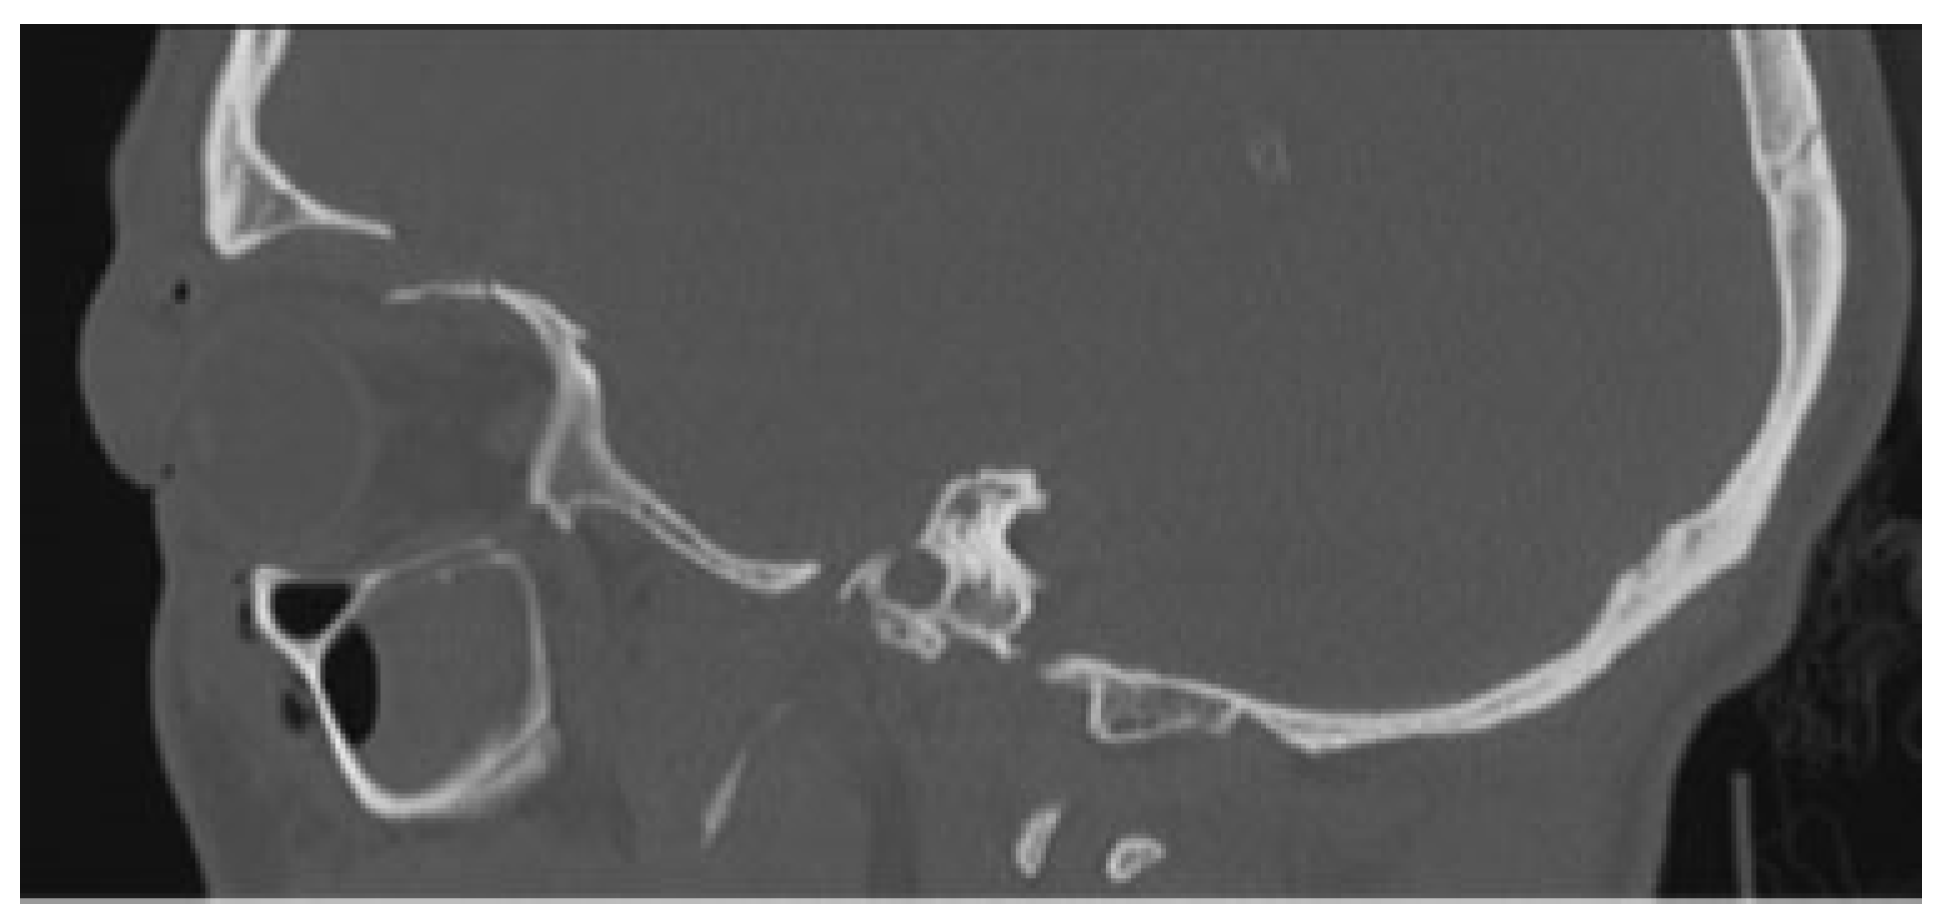

The first case is about a 22-year-old male who was involved in a high-energy trauma, scooter versus parked car. When the ambulance arrived, the patient had a maximal Glasgow coma scale despite of the fact that he had not been wearing a helmet. The patient was seen according the Advanced Trauma Life Support protocol. During the primary survey in the emergency room, there were no evident injuries to the neck, chest, abdomen, or extremities. In addition, the patient had no vision loss, no diplopia, and the sensitivity of the forehead was intact. The computed tomography (CT) showed an impression of the left frontal bone with contusion of the brain and an orbital medial wall fracture without dislocation on the left side and an orbital roof fracture on the left side with downward displacement of the fragment (

Figure 1 and

Figure 2) Despite the dislocated orbital roof fracture, it was decided to keep him under observation.